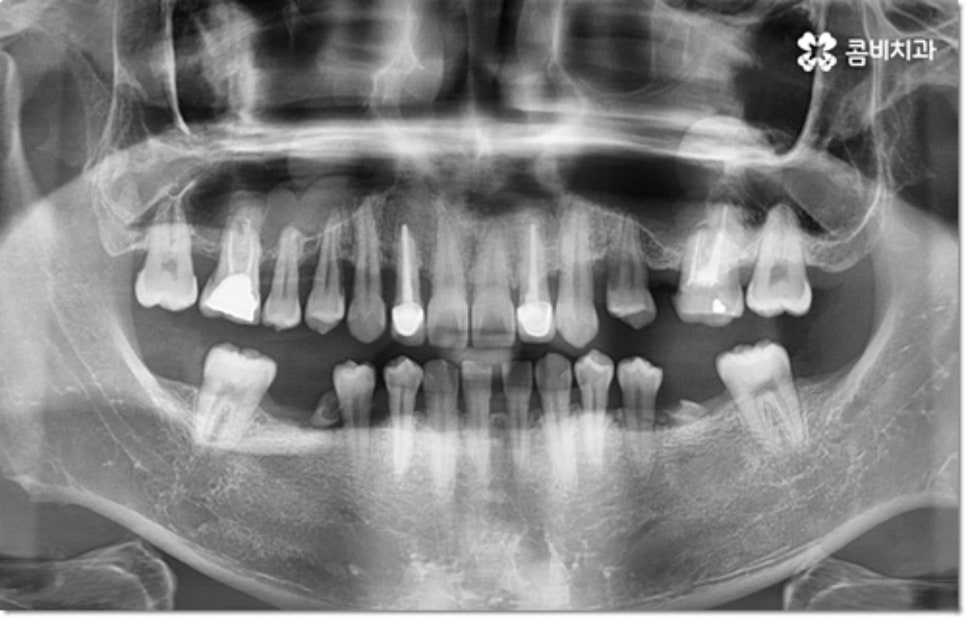

사진에서 볼 수 있는 사례는 아랫니가 크게 부러져서 빠졌을 때 아랫니임플란트 시술을 통해 수복을 해 준 거예요. 이때 빠른 일상 복귀를 원하는 만큼 기간이 얼마나 오래 걸리는가 하는 것은 임플란트 시술을 받으시는 분들의 가장 주된 관심사 중 하나라고 할 수 있는데요.

임플란트 시술 기간은 환자분들의 상황에 따라 달라지는 것이지만 보통 빠르면 36개월, 뼈이식이나 상악동 거상술과 같은 선처치가 필요한 경우 또는 회복 기간이 생각보다 오래 걸리는 경우에는 8개월1년 넘게 까지도 걸릴 수 있습니다. 혹시 모를 부작용으로 재시술을 받게 되는 경우도 있기 때문에 치과를 선택하실 때 말씀드린 의료진의 숙련도 외에도 여러 가지 사항들을 꼼꼼하게 따져보실 필요가 있어요. 3D CT 와 같은 정밀 장비로 환자분들의 잇몸 상황 또는 교합 등을 세밀하게 살펴보고 그에 맞춰 무리하지 않게 임플란트 식립을 진행하는 치과에서 검진부터 사후관리까지 체계적으로 케어받는 것이 중요한 거예요.